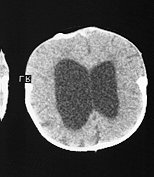

• often, hydrocephalus

• ventriculomegaly